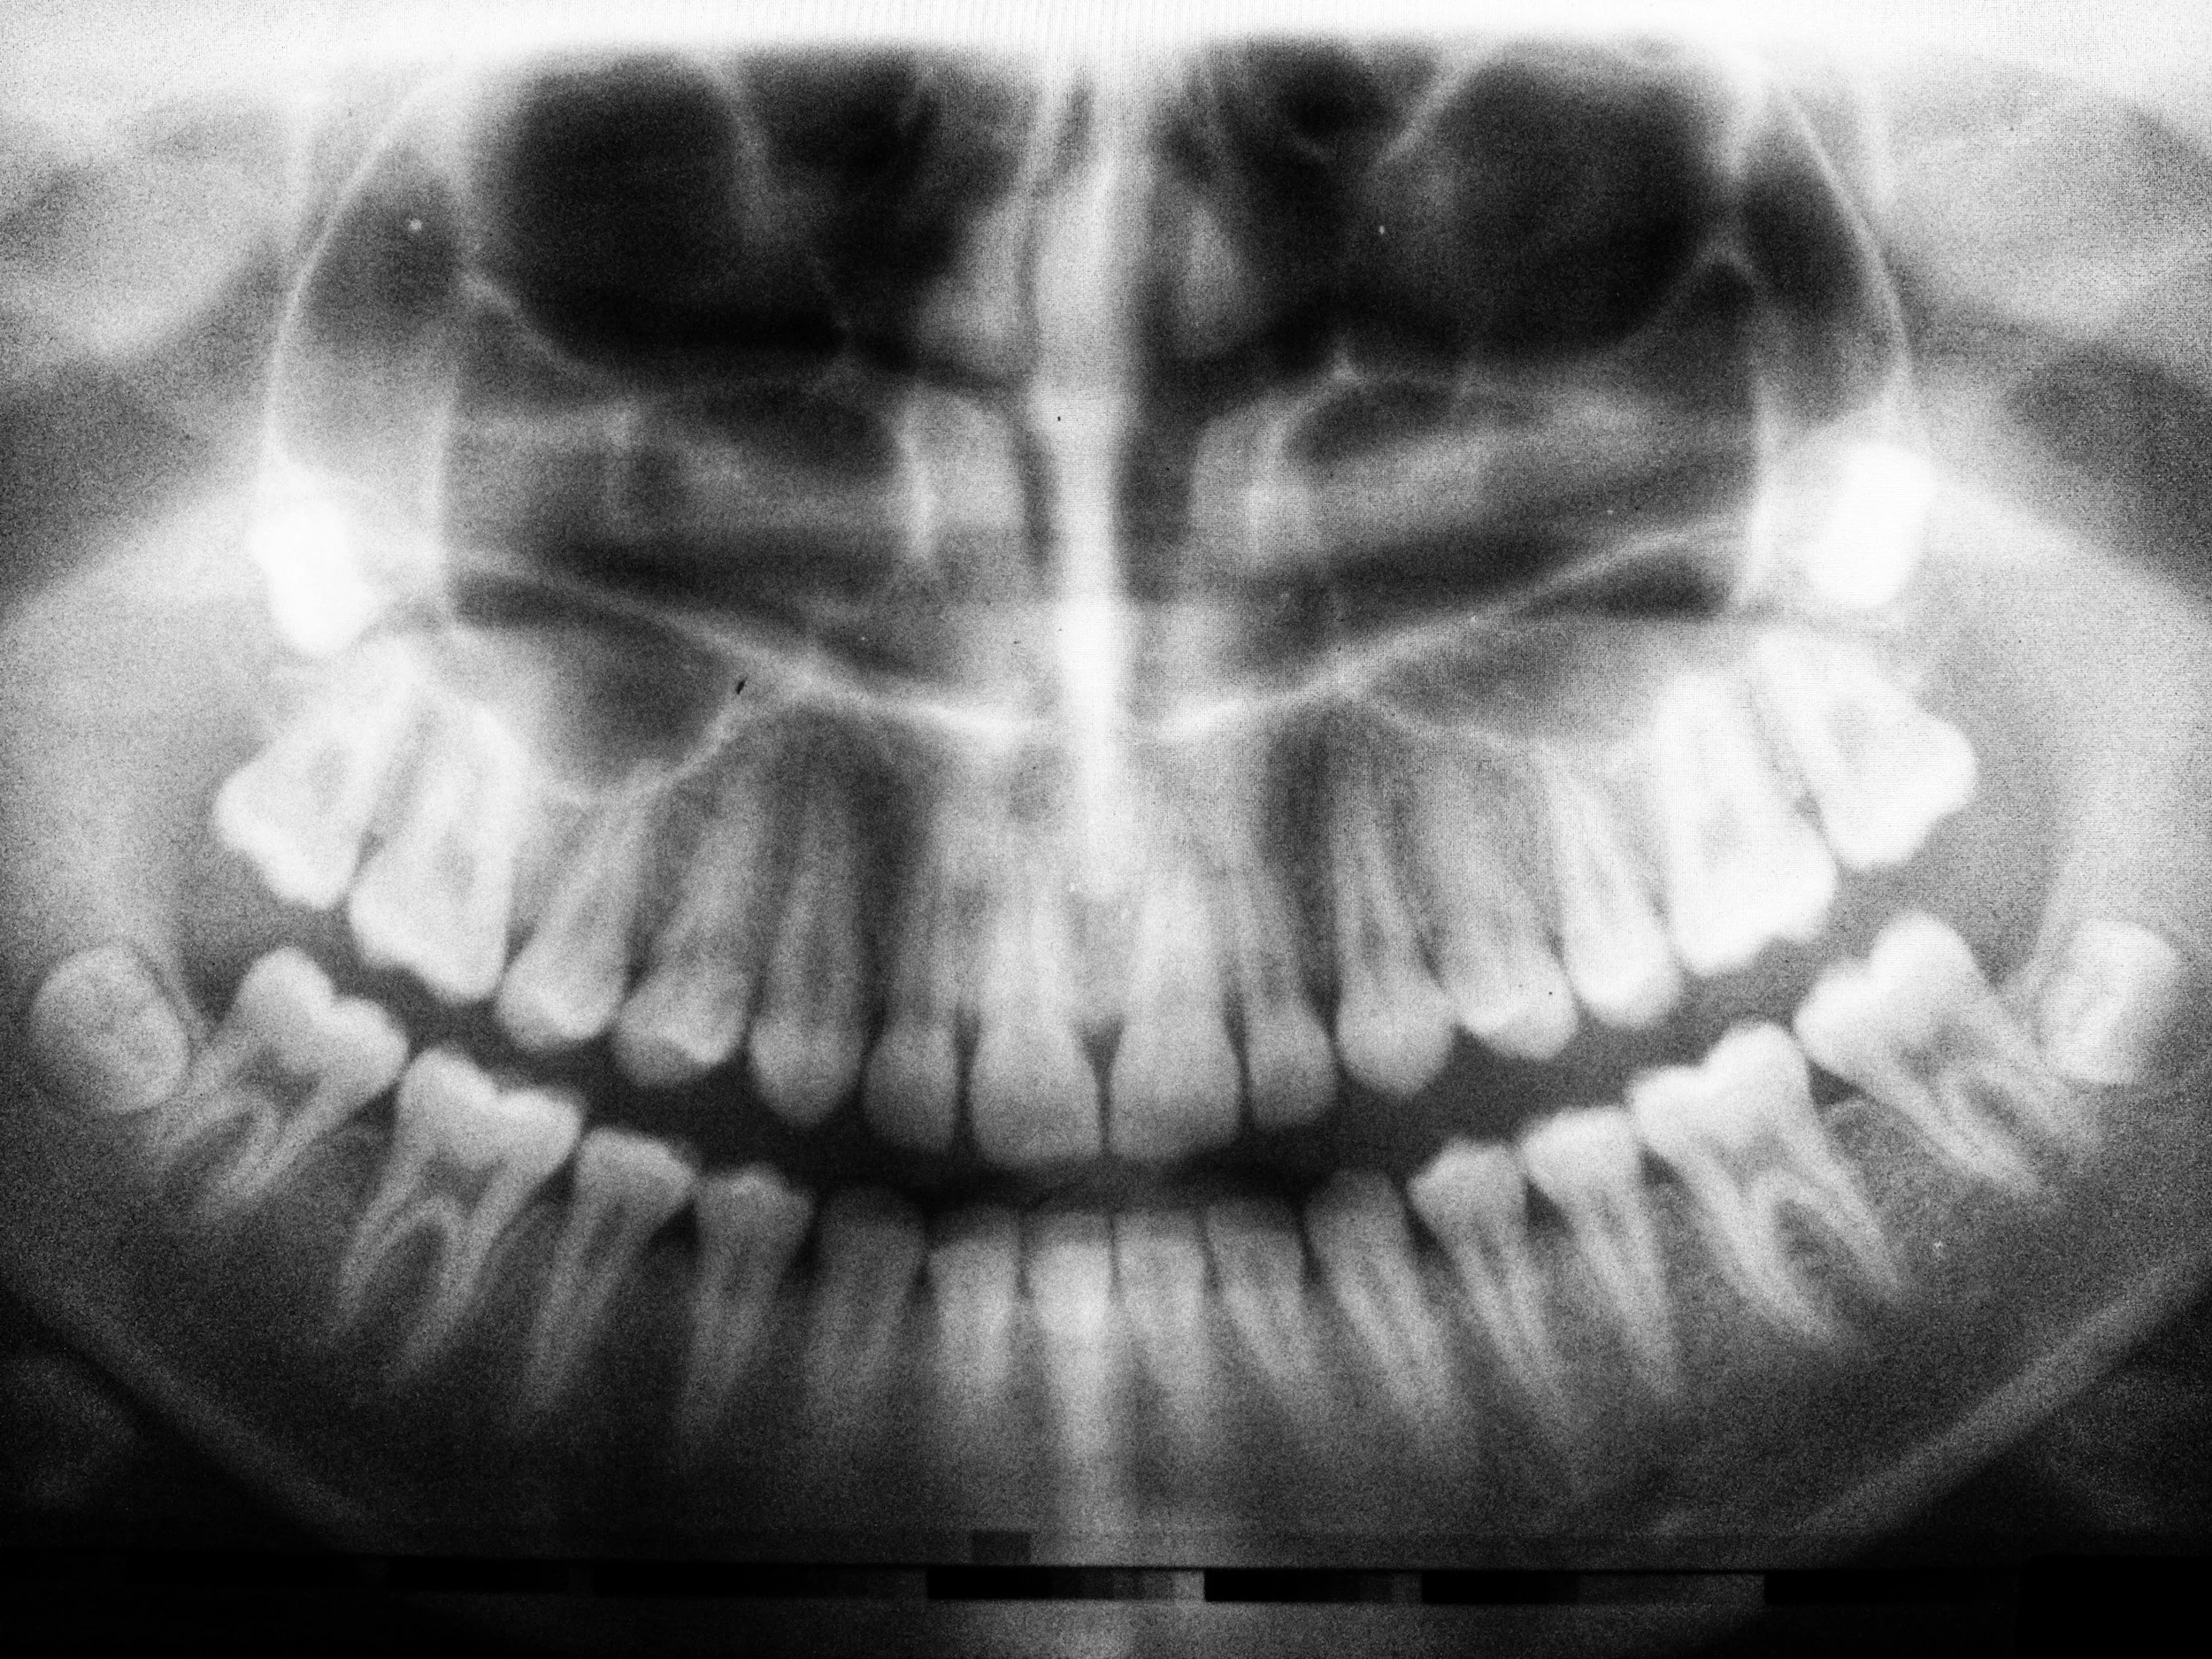

Digital radiography (digital x-ray) is the latest technology used to take dental x-rays. X-rays are an essential part of any dental care treatment plan. They are diagnostic, but they can also be preventative, by helping a dentist diagnose potential oral care issues in a patient’s mouth before they become a major problem. Digital dental x-rays are essential, preventative, diagnostic tools that provide valuable information not visible during a regular dental exam.

Dental x-rays may reveal:

• Abscesses or cysts

• Check the health of the bony area around the tooth

• Cancerous and non-cancerous tumors

• Tooth and root positions

• Find cavities between and on the teeth

• Status of developing teeth

• Evaluate injuries to the teeth after trauma

• Monitor good tooth health through prevention

• Find if teeth have bone loss or periodontal disease

• Visualize teeth that are malposed or impacted

Detecting and treating dental problems at an early stage may save you time, money, unnecessary discomfort, and your teeth!